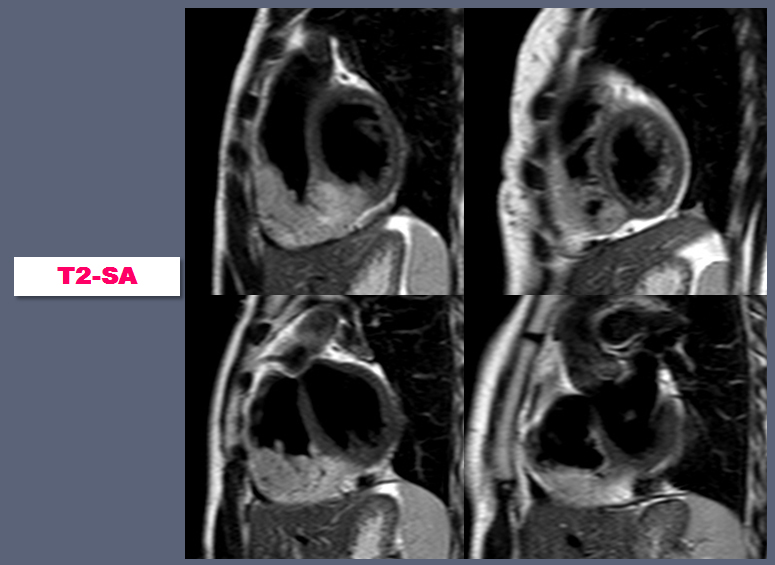

| 22yr / F, C.C. : Chest pain for 5 years, Anterior, mid-chest area, Aggravated by exercise, improved by resting, Dizziness (+), Palpitation (+) |